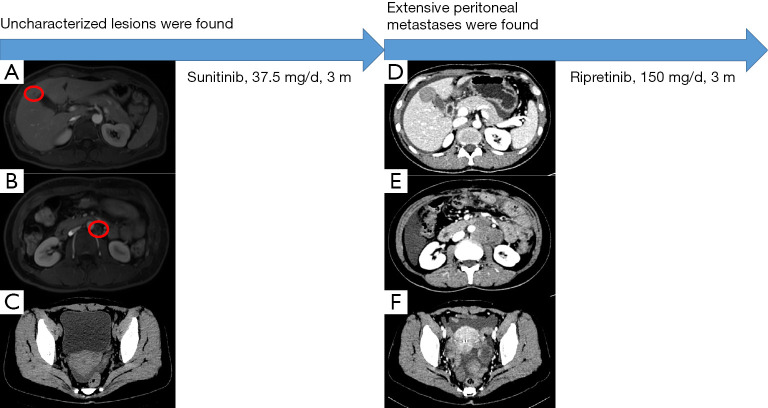

鉴于肿瘤对伊马替尼有耐药性,患者在手术后口服舒尼替尼(37.5 毫克/天)。 患者状态良好,未发生药物不良反应。 2021 年 1 月的腹部 CT 扫描未见明显异常。 2021年5月腹部磁共振复查示肝右前叶异常信号,较2021年1月结果新,考虑血管瘤可能性大(见图2A)。 此外,在腹主动脉左侧观察到淋巴结肿大(见图 2B),还有少量盆腔积液(见图 2C)。

患者2021年8月的腹部CT显示腹部和骨盆多处软组织结节和肿块,与2021年5月的结果相比是新的,考虑转移。 肿瘤基因解码医师还注意到肝脏右前叶的低密度病灶比以前更大,并考虑转移(见图2D)。 此外,在腹主动脉周围观察到多个肿大的淋巴结,并考虑转移(见图2E),并且还观察到腹部盆腔积液(见图2F)。 鉴于患者肿瘤的基因突变类型,患者从三线 TKI 瑞戈非尼中获益的可能性很小,因此患者接受了口服利培替尼(150 mg/天)治疗。 2021年10月,患者继续服药,状态良好但有轻微腹胀。 她将如期接受审查。